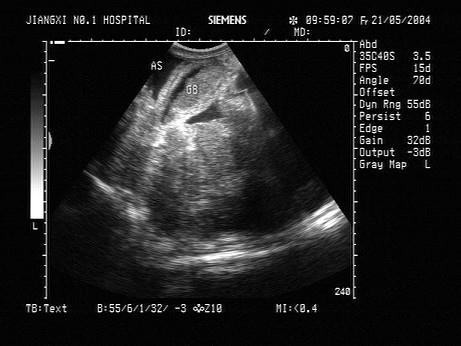

问题 男,36岁,患乙肝大三阳十多年,现发现腹腔内大量腹水。声像图如图所示,结合超声声像图,诊断为?(?)

选项 A.急性化脓性胆囊炎,胆汁淤积 B.慢性肾病引起低蛋白血症,胆囊壁水肿,胆汁淤积 C.肝硬化所致低蛋白血症,胆囊壁水肿,胆汁淤积 D.心衰引起胆囊壁水肿,胆汁淤积 E.胆囊癌

答案 C